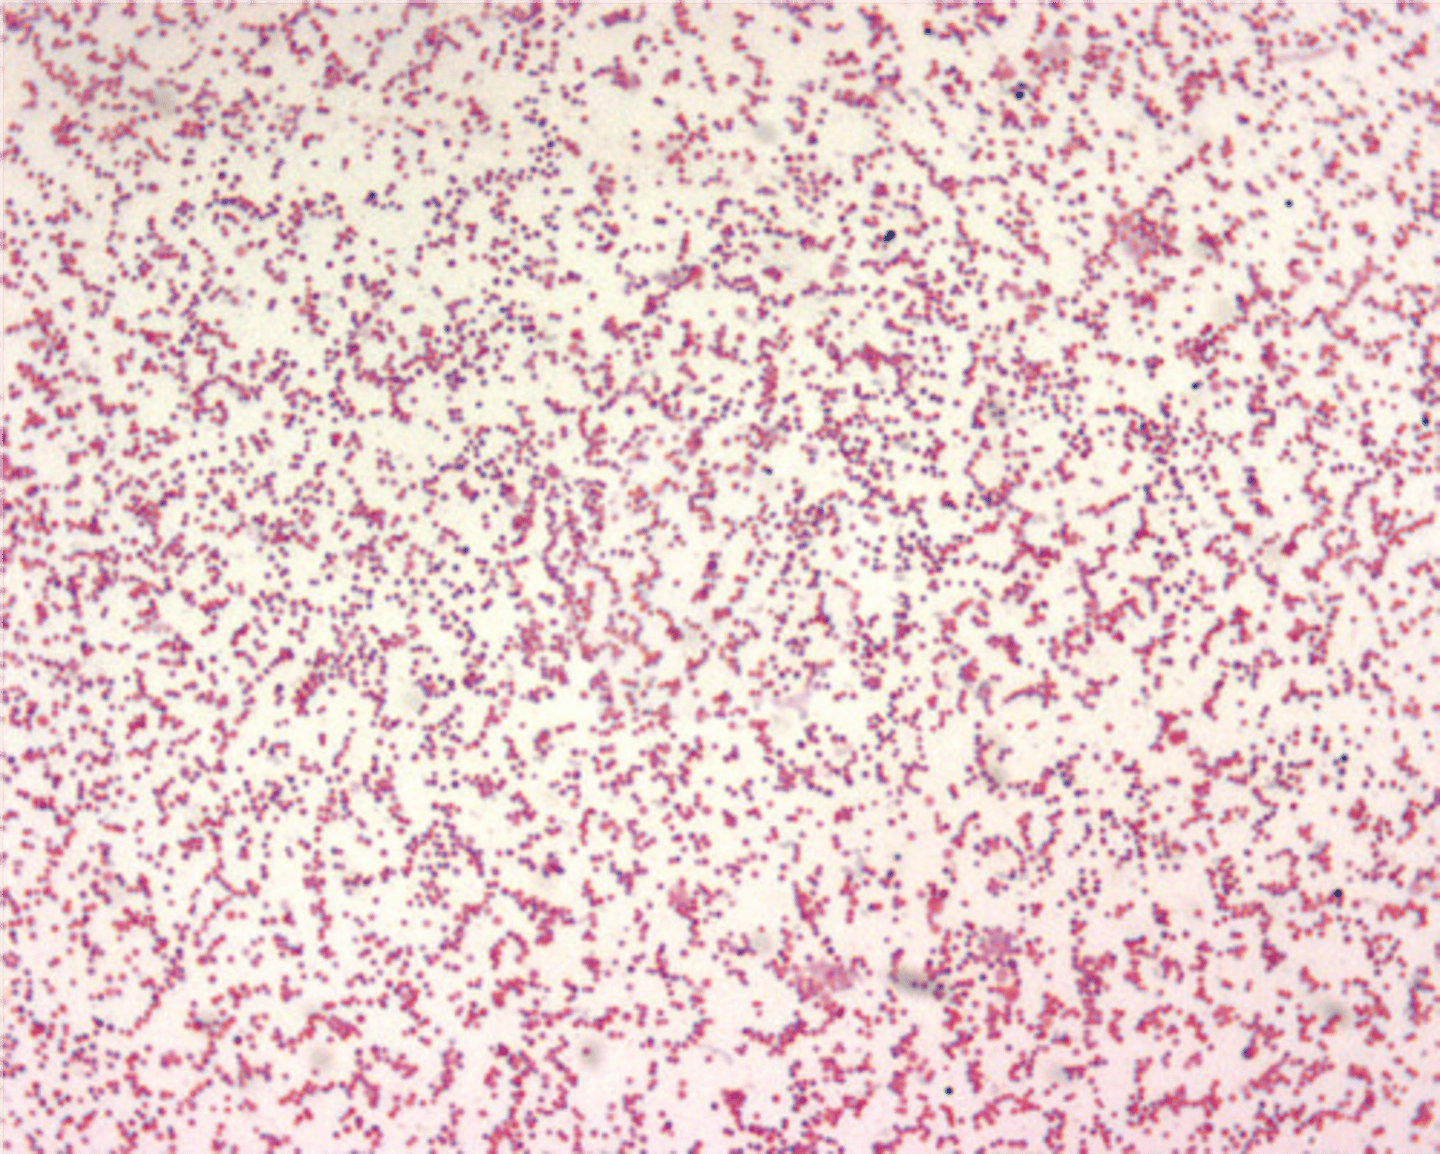

Borrelia burgdorferi Stain

Gram negative spirochete

Borrelia burgdorferi Disease

Lyme Disease